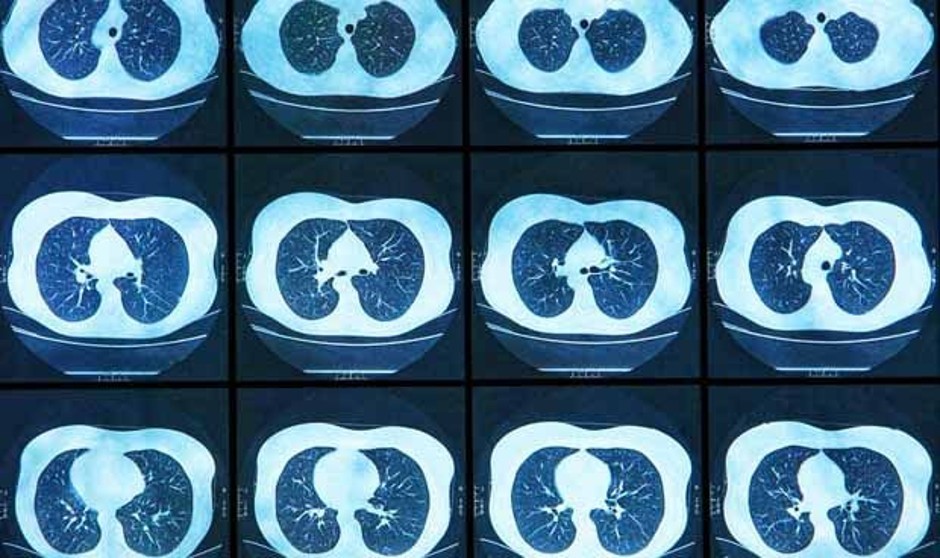

El proyecto Cassandra (Cancer Screening, Smoking Cessation and Respiratory Assesment), que busca impulsar un programa piloto de cribado de cáncer de pulmón en España con el objetivo de reunir la evidencia científica necesaria para incluir esta detección precoz en la cartera de servicios del Sistema Nacional de Salud (SNS), se encuentra en una fase de letargo a la espera de Sanidad. Según ha podido saber Redacción Médica, la reciente reunión entre el Ministerio y los representantes de Cassandra ha sido “muy positiva”, pero no se han concretado detalles más allá de la buena acogida del proyecto y un emplazamiento a futuras reuniones una vez los dirigentes sanitarios hayan estudiado su viabilidad y si finalmente deciden respaldarlo…